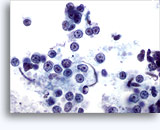

Abbildungen 37-38: Dissoziierte Einzelzellen mit hoher KP-Relation, schmalem Zytoplasmasaum, lockerem Chromatin, Kernprotrusionen und kernnahen Nukleolen. Im Hintergrund lymphoglandular bodies.